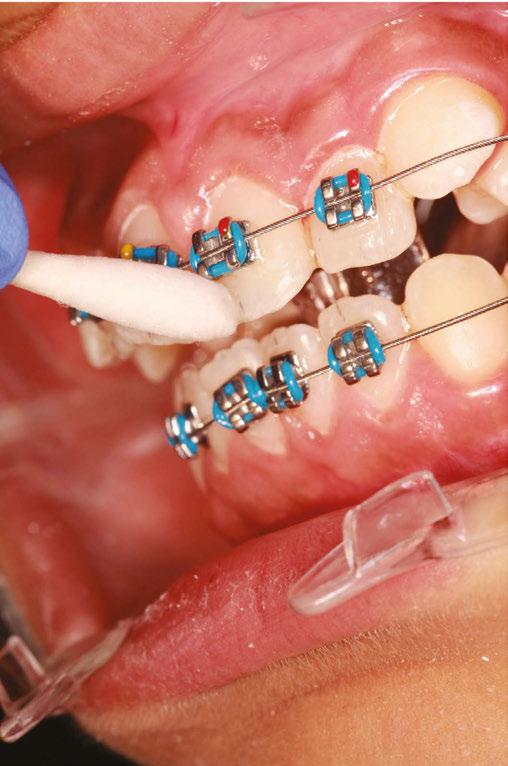

Treatment started with a transpalatal arch between the maxil lary first molars, which acted as a rigid unit to prevent unwanted facial inclination of the molars. A referral was made to an oral surgeon to remove the third molars. Fixed appliances of .022 x .028 Pinnacle® brackets with the McLaughlin, Bennett & Trevisi Prescription from Ortho Technology® were bonded to maxillary and mandibular teeth, and .014 thermal nickel-titanium fullform archwires (TruFlex®, Ortho Technology®, West Columbia, South Carolina) were used to align the arches after which a .016 stainless steel maxillary TruForce™ wire (Ortho Technology®) was placed. Following the stainless steel wire, two Vector TAS infrazygomatic miniscrews (Ormco™ Corporation, Orange, California) were inserted between the first and second maxillary molars (Figures 4A-4E).

Power chains with approximately 150 grams-force were added from the miniscrews to the maxillary first molars. After a .019 x .025 TruForce™ stainless steel archwire was placed in the maxillary arch, an additional power chain connected the maxil lary canines to the miniscrews to retract as well as to intrude the posterior buccal segments without jeopardizing the inclination of the maxillary anterior teeth. The patient refused the use of miniscrews in the mandibular arch, so molar bite blocks (Reli ance® Ultra Band-Lock, Ortho Technology®) controlled the ver tical position of the mandibular molars, which prevented them from over One-eightheruption.inch

vertical elastics (Amber medium 1/8 inch Manta Ray®, Ortho Technology®) and Class II 3/16 inch medium elastics (3/16 medium Sea Otter®, Ortho Technology®) were employed in the last stages of treatment to settle the occlusion and to improve the mandibular incisor inclination (Figures 5A-5C).

Figures 3A-3C: Cephalometric tracing before and after treatment and superimposition Figures 4A-4E: Infrazygomatic miniscrews inserted in the upper jaw Figures 5A-5D: Finishing and detailing the occlusion with a progress pan oramic X-ray B. C.Wraparound Hawley Retainers provided retention, which encouraged further molar eruption and intercuspation. Once molar intercuspation completes, new thermoelastic refiners would be used to prevent molars from over eruption.